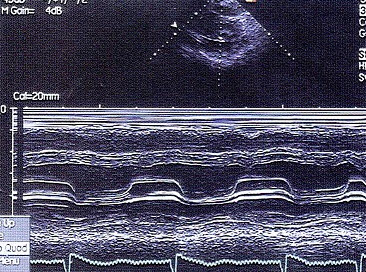

该M型图提示()

A.风湿性心脏病二尖瓣狭窄